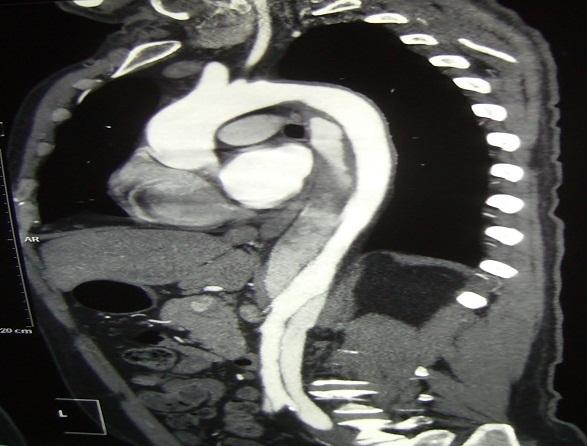

[Dissection of the descending thoracic aorta and abdominal aorta in Takayasu's arteritis: report of a case].

https://cdn.ncbi.nlm.nih.gov/pmc/blobs/7261/4228997/a80b7771a328/PAMJ-17-196-g001.jpg